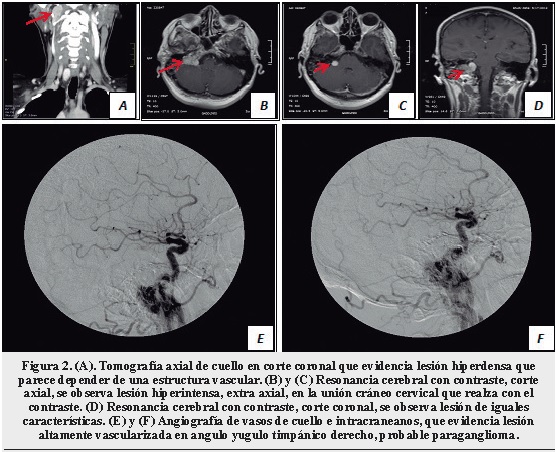

Se realizó una Tomografía axial de cuello, que evidencio una lesión hiperdensa, retrofaringea, en el angulo yugulo timpánico, que parecía depender de una estructura vascular, y que era congruente con los hallazgos de la resonancia cerebral. La resonancia mostró una lesión extra axial, que comprometía algunas estructuras óseas de la base del cráneo. La angiografía de vasos de cuello, evidenció una lesión altamente vascularizada, retrofaringea, del angulo yugulo timpánico, que por las características radiológicas sugería un paraganglioma (Figura 2). Los hallazgos imagenológicos eran congruentes con las alteraciones del examen neurológico, por lo que se confirmó el diagnóstico de síndrome de Villaret secundario a un paraganglioma del espacio retrofaringeo.

Durante la última década se ha logrado establecer, que aproximadamente un tercio de los paragangliomas están determinados genéticamente, y se han descrito mutaciones en genes específicos relacionados con la enzima succinato deshidrogenasa (10). Estas neoplasias se caracterizan porque en las neuroimagenes existe evidencia de infiltración, erosión ósea y un realce significativo con el medio de contraste. En la arteriografía, esta se caracteriza por ser una lesión hipervascularizada, que en la mayoría de los casos depende del sistema arterial carotideo interno o externo (8). El tratamiento quirúrgico es el de elección, sin embargo, la radioterapia puede ser una opción cuando está contraindicada la cirugía (11).